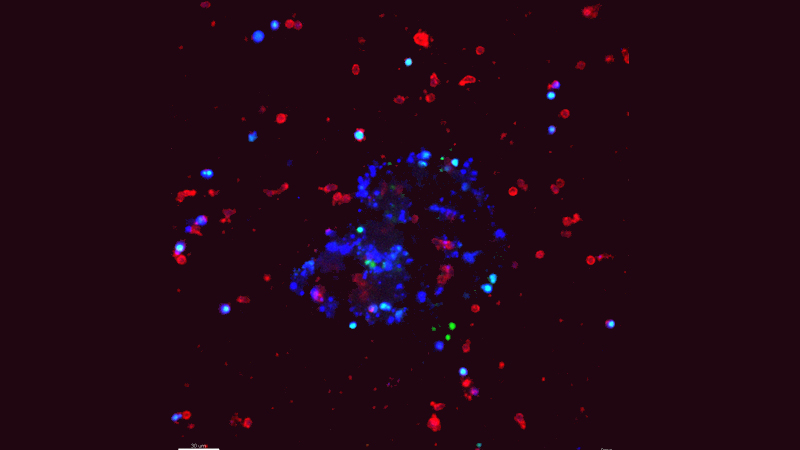

Natural killer (NK) cells, a type of immune cell, are known to limit metastasis by inducing the death of cancer cells. But metastases still form in patients, so there must be ways for cancer cells to escape. Using a novel cell culture method developed by lead author Isaac Chan, MD, PhD, a medical oncology fellow at Johns Hopkins, the researchers studied the interactions between NK cells and invasive breast cancer cells in the laboratory in real time. They discovered that metastatic breast cancer cells can reprogram NK cells so that they stop killing cancer cells and, instead, assist in metastasis.

Using molecular profiling and computational analyses developed by Joel Bader, PhD, professor of biomedical engineering at the Johns Hopkins Institute for Basic Biomedical Sciences and Institute of Genetic Medicine, and Hildur Knútsdóttir, a fellow in Bader’s lab, Ewald said they were able to map every suspected molecular interaction between immune cells and cancer cells — and identify the ones that were likely regulating this communication.